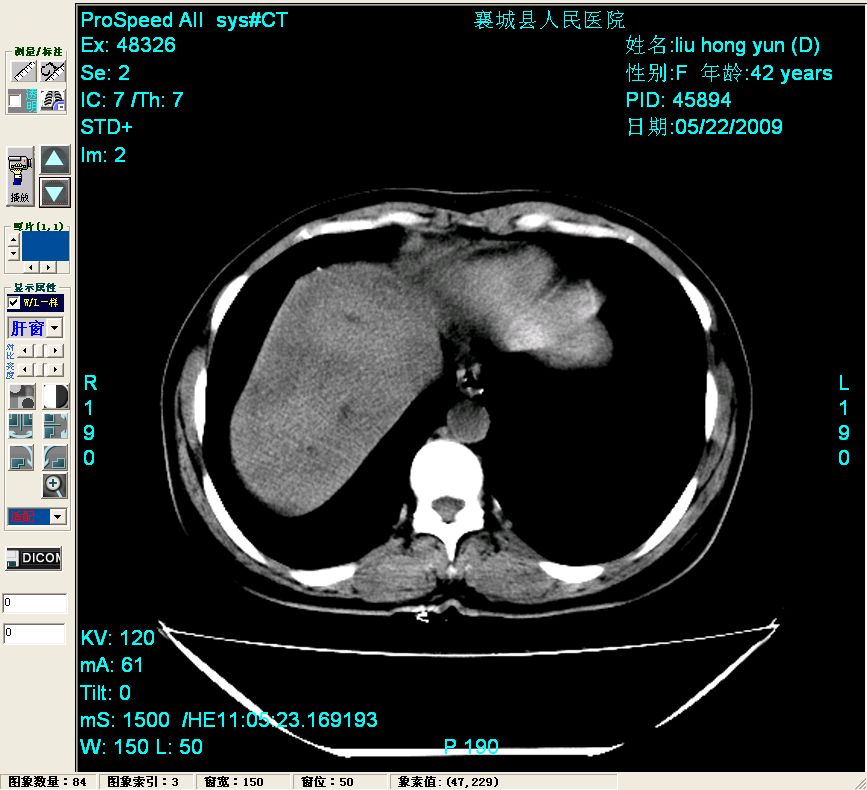

平扫:

平扫左肝外叶体积显著减小,左肝外叶见多房囊性低密度区,左肝实质及右肝前叶浅表实质呈低密度改变,左肝及右肝前叶胆管扩张,脾大

2左肝及右肝前叶表现考虑胆囊摘除术后所致的肝动门脉瘘形成,慢性纤维组织炎性增生.不完全除外左肝胆管细胞癌